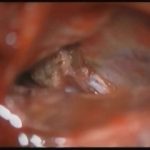

術中写真

摘出 前

摘出 中

摘出 後